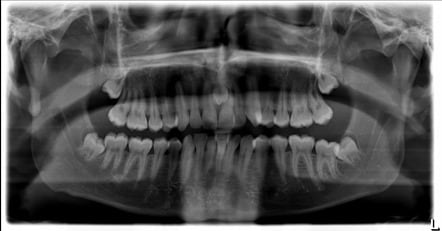

Freddie Mercury nació con algo conocido como mesiodens, término que se usa para señalar que una persona nació con varios dientes extra.

En el caso de Freddie Mercury contaba con 4 incisivos de más (dos en cada lado de la dentadura), lo cual desplazó el resto de sus dientes hacía adelante.

Por si esto fuera poco, sus dientes frontales eran de mayor tamaño que lo habitual; lo cual hizo que, junto al movimiento de su dentadura, sobresalieran de manera evidente.